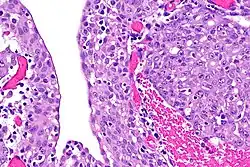

| Renal medullary carcinoma (right of image), reactive urothelium and sickled red blood cells. H&E stain. | |

The finding that virtually all people affected by renal medullary carcinoma carry at least one copy of the HbS mutation suggests that sickle cell trait somehow predisposes to this type of cancer.[5] The precise mechanism is unknown, but red blood cells with a sickle cell configuration have been identified in pathology specimens.[2]

The diagnosis of renal medullary carcinoma is typically made after individuals with sickle cell trait present with the typical signs and symptoms outlined above, in combination with radiographic imaging (usually abdominal/pelvic CT scan) studies and ultimately surgical biopsy and pathological examination of the tumor. Findings on radiographic examination are non-specific and can reveal a mass deep within the kidney.[6] Histopathology studies show a distinctive pattern that can be distinguished from other renal tumors.[1]